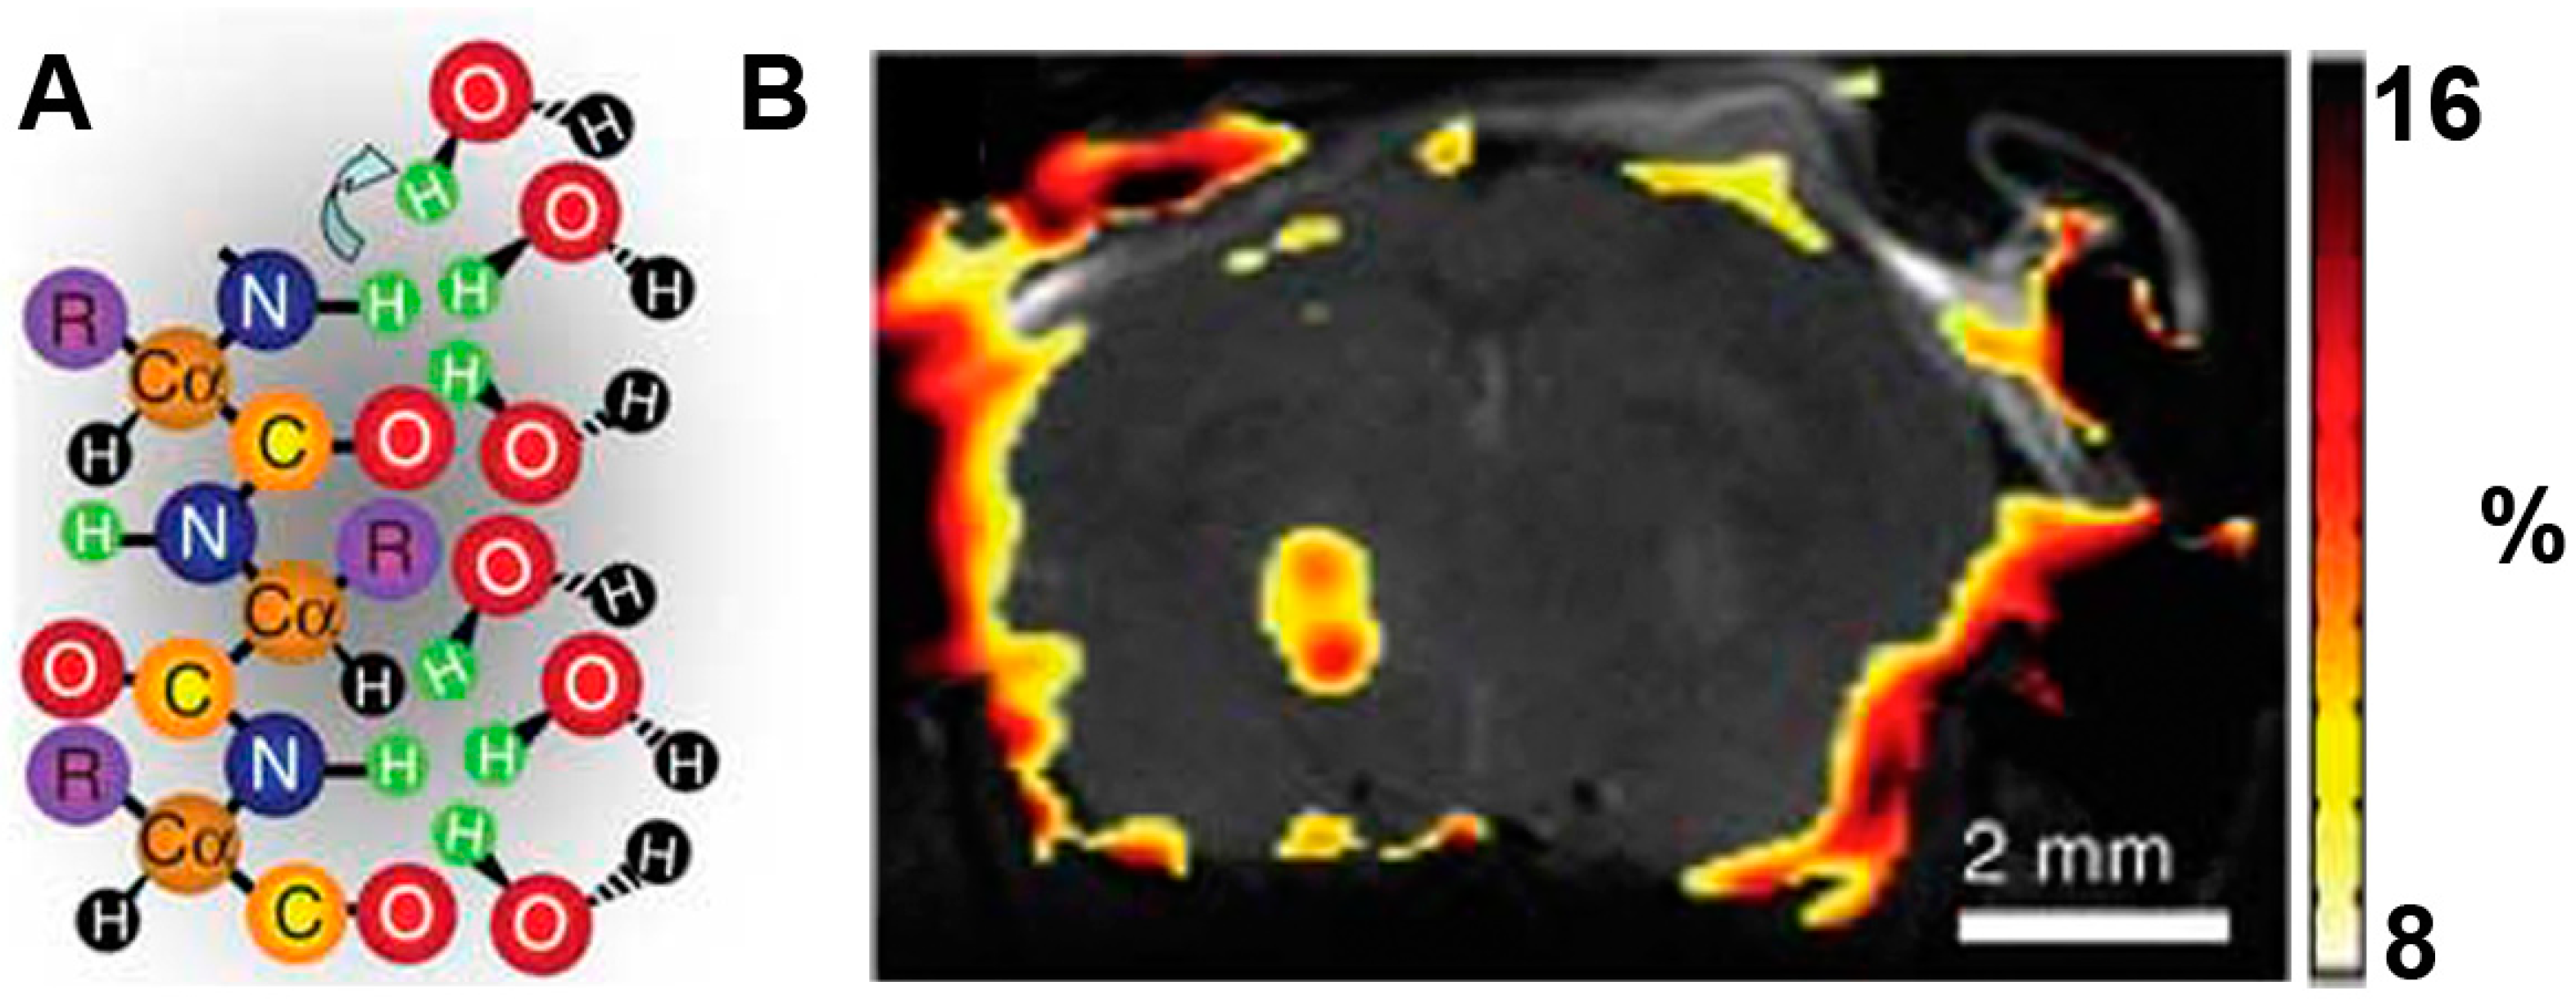

In recent years, researchers have developed many CEST MRI reporter genes [20,69]. For example, a novel artificial gene, lysine-rich protein (LRP) with a high percent of lysine residues was designed to image the transgene overexpression of the glioma cells in vivo. Frequency-selective radiofrequency pulses then label the amide protons and reduce exchange with water protons. This decreases MRI signal intensity [20] (Figure 4). Although CEST is a new detection method and offers ways to image embedded exchange and relaxation mechanisms in tissue, the energy deposition in tissue (specific absorption rate: SAR) and the millimolar sensitivity of the technique still limit its clinical use. Generally, a reporter gene encodes to a longer protein. This will give a higher CEST signal via a commercially available full-length synthetic gene. The reporter targets with reduced charge and increases the exchange rate to allow increased detection sensitivity. In addition, frequency-specific reporter genes may be designed to include imino, amine and guanidine protons. This suggests that multiple labeling is possible. It is reasonable to expect that CEST will soon become a standard clinical protocol [20].

Figure 4.

LRP reporter gene imaging of glioma based on CEST MRI. (A) Frequency-selective radiofrequency pulses label the amide protons (green); (B) Signal intensity-difference map of phantoms. LRP-transfected rat glioma cells were confirmed by Gilad A et al. in the overlaid CEST SI difference map [20].